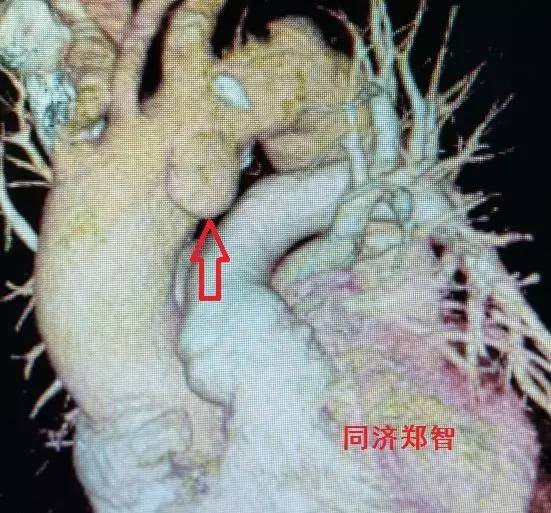

三维重建显示主动脉弓穿透性溃疡,与图11为同一病人(图12)。

图12